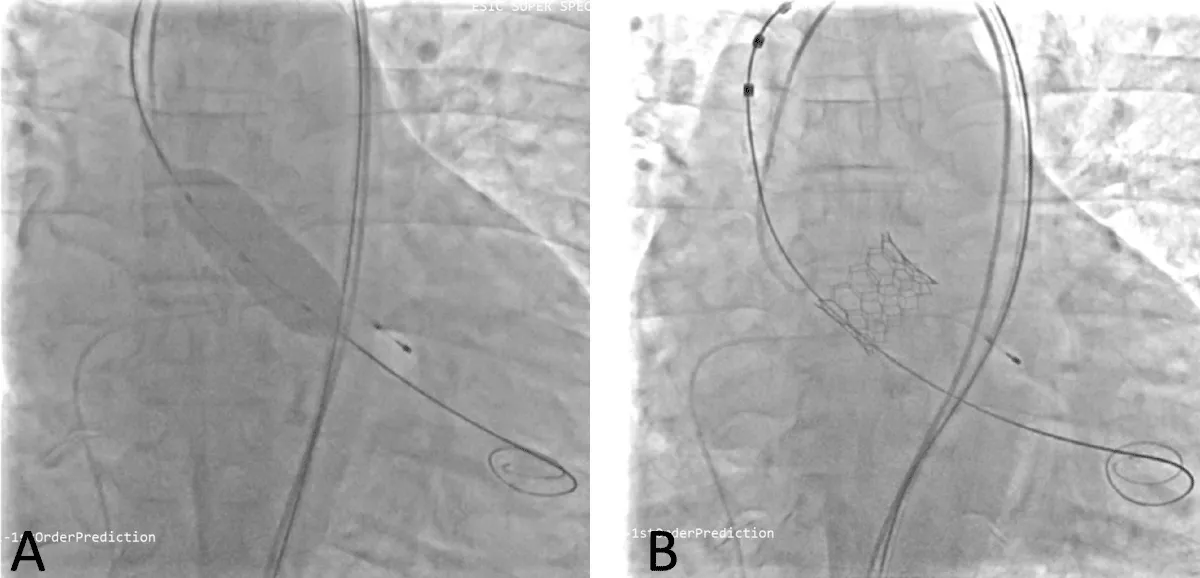

He was planned for double valve replacement (DVR), but the patient declined due to the high surgical risk. Therefore, he was considered for staged BMV and Transcatheter aortic valve replacement (TAVR). Pre-procedural planning was done for TAVR, and after ensuring the patency and adequacy of femoral vessels, he underwent a coronary angiogram (CAG), which showed normal coronaries. Following consent, the right femoral vein was accessed. A transseptal puncture was performed with a broken Brough needle, and the LA wire was parked. The MV was dilated with a 26 mm Inoue balloon (Figure 7), resulting in a reduction of the MV gradient from 24/10 mm Hg to 9/5 mm Hg and an increase in MV area from 0.9 cm2 to 1.6 cm2. There were no post-procedural complications. After 1 month, he underwent TAVI. Both right and left femoral artery access was obtained. Following pre-dilatation of the AV with an 18 mm balloon, TAVR was performed using a 26 mm balloon-expandable valve (Myval, Meril Lifesciences, Vapi, Gujarat, India) (Figure 8) (Video 3), followed by post-dilatation under accelerated right ventricular pacing (180 bpm). ECHO and final aortography showed no paravalvular leakage after device release (Figure 9).

Figure 7: Fluoroscopic image of LA wire passed through atrial septal puncture (A) and Balloon dilatation of the mitral valve with Inoue balloon (B).

Figure 8: Fluoroscopic image of Balloon dilatation of the aortic valve (A) followed by aortic valve implantation (B) under right ventricular pacing.